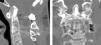

We demonstrate the case of a surgery in a patient with irreducible atlantoaxial dislocation (IrAAD) after C2 fracture. The challenges of this case were the flexed head in a forced position, impossibility of neck extension, and revision operation after posterior occipito-cervical fixation. The patient underwent the following surgeries: 1. A ventral release of C1-C2 using transcervical endoscopy; 2. Removal of occipito-cervical system and fibrous block resection in the posterior surfaces of the C1-C2; 3. Reducing of AAD and odontoid screw fixation; 4. Posterior C1-C2-C3 screw fixation. Ankylosing of C1-C2 and C2-C3-C4 fusion was verified by computed tomography scan. There was an improvement in patient status as observed by the increase of the SF-36 scale scores.